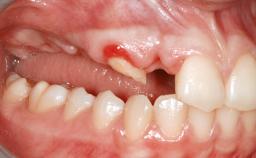

A woman in her mid-fifties was referred by a dental student for dental implant placement. Both posterior segments of the mandible had been edentulous for more than 4 years, the only residual tooth being the right lower first premolar. The patient had used a removable partial denture but was not entirely satisfied with its function. The clinical examination revealed a sharp edentulous ridge in both posterior segments of the mandible, and the patient was told that it would not be possible to insert implants into this thin edentulous ridge without significant augmentation of the alveolar ridge. Her medical history revealed no significant findings and no underlying disease that might have complicated surgical procedures. During the presurgical examination, the patient reported that she was a little apprehensive about bone grafting. After being informed about the surgical procedures and potential postoperative complications, she accepted the proposed surgical plan of bone grafting and subsequent placement of implants.